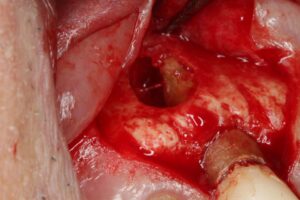

膿疱摘出中

膿疱摘出後

根の先端を切除

外科的に病巣を取り出し、感染源である根の先端を一部切除して消毒、封鎖した